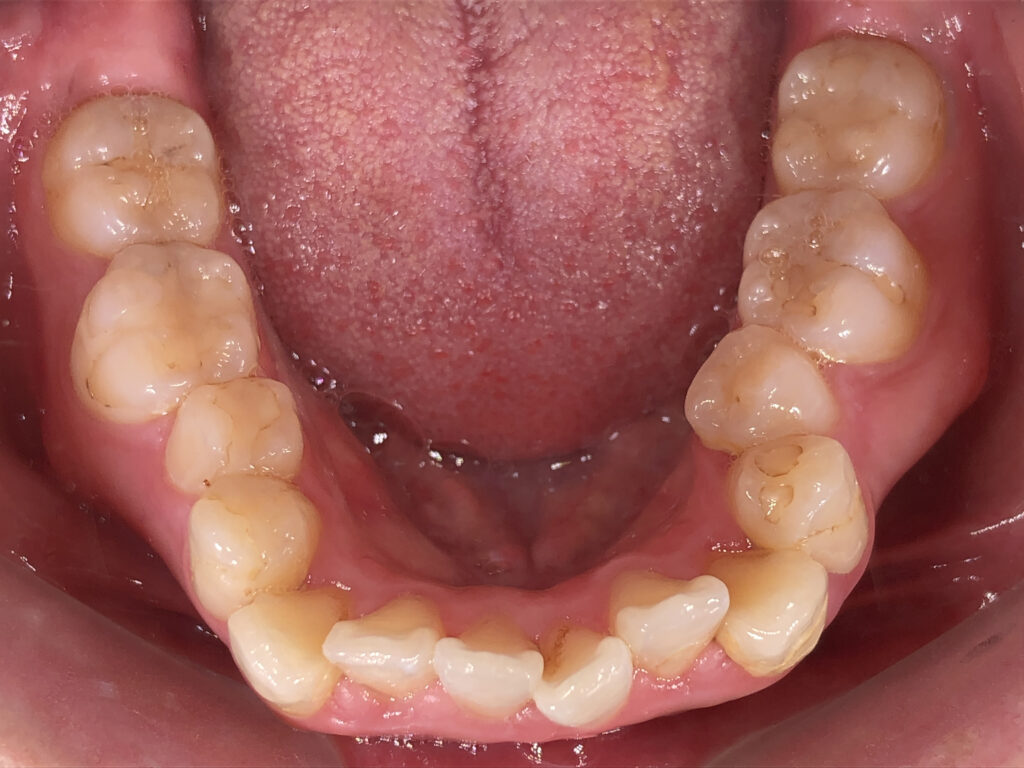

下顎

治療前

治療後